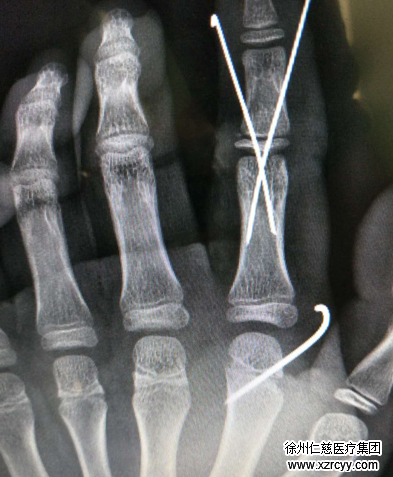

尚医生轻声安慰:“别慌,别慌。”一边迅速检查孩子的手指,左手示指从中节指骨基底部离断,左手第二掌骨骨折,血管、神经、肌腱都有损伤。尚医生立即申请了绿色通道,让孩子在最短的时间内接受再植手术。

从18:09到21点多,手术进行了3个多小时。考虑到孩子比较小,以后还要生长发育,尚医生手术团队在手术时给他保留了关节,用克氏针打入固定,把断裂的伸肌腱和屈肌腱接起来,把血管、神经一一接好,最终通血良好。

术中,又对孩子左手背的第二掌骨头端骨折,进行复位后打了钢针固定。